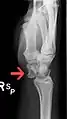

Dislocated lunate